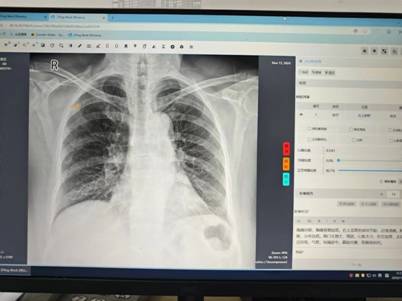

江苏省卫生健康云影像平台作为省级重点惠民医疗信息化工程,构建起全省医学影像数据共享体系,具备影像存储管理、跨区域调阅共享、检查结果互认及重复检查预警等功能,能够对胸部 X 光、CT 等影像进行智能分析。在肺结核早期诊断中,该平台的 AI 智能阅片系统通过抓取胸片关键信息并反馈诊断结果,一旦与原诊断存在差异,医院将立即组织专家复核,必要时安排进一步检查或转诊上级医院,有效减少漏诊误诊,提升基层结核病发现率。

我市积极推动基层医疗卫生机构应用省云影像平台 AI 诊断技术,为结核病防治工作开拓新路径、注入新动能。2024 年,全市已有 5 家基层医疗卫生机构完成省云影像平台 AI 诊断技术部署并投入使用。今年 5 月,又有 14 家基层医疗卫生机构成功纳入省云影像平台 AI 技术系统,目前正有序推进接入工作。下一步,我市将加快申报机构的系统对接与技术落地,充分发挥 AI 技术在肺结核早诊早治中的优势,全力提升早期筛查与临床诊断的精准度和时效性。